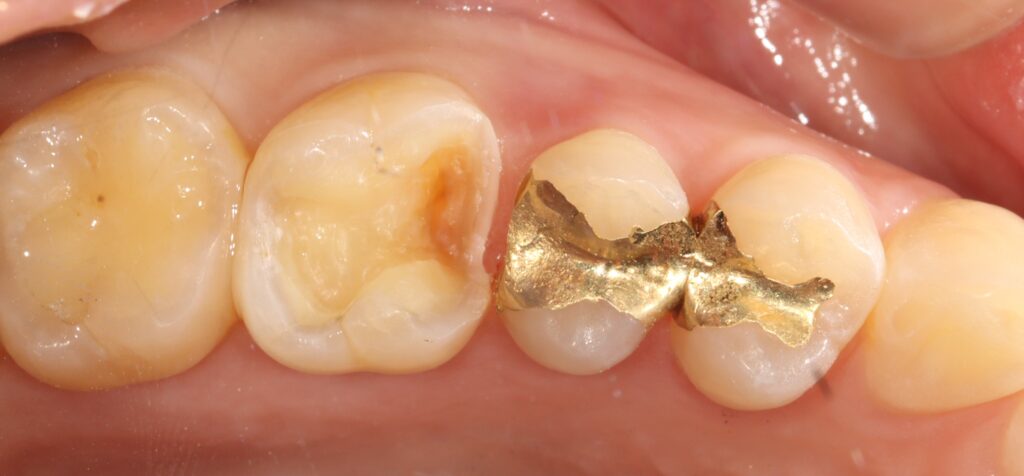

이번 증례는 기존 금 인레이가 수복되어 있던

치아에서 재치료가 필요했던 경우로,

기존 보철물의 변연 적합도가 떨어지거나

2차 우식이 발생한 상황이었습니다.

오래된 금 인레이는 내구성 면에서는

장점이 있지만 시간이 지나면서

주변 치아와의 경계 부위에서 미세한 틈이 생기거나,

심미적인 측면에서 부담을 느끼는 경우가 많습니다.

이에 따라 기존 보철물을 제거하고

내부 상태를 확인한 뒤, 우식 조직을 깨끗하게

제거하는 과정이 선행되었습니다.